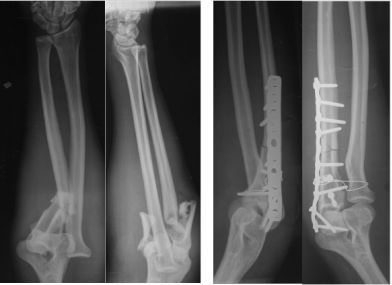

胫骨远端简单骨折选用钢板固定没有实现坚强固定,钢板承受应力,孔处应力集中断裂

更换长钢板后愈合